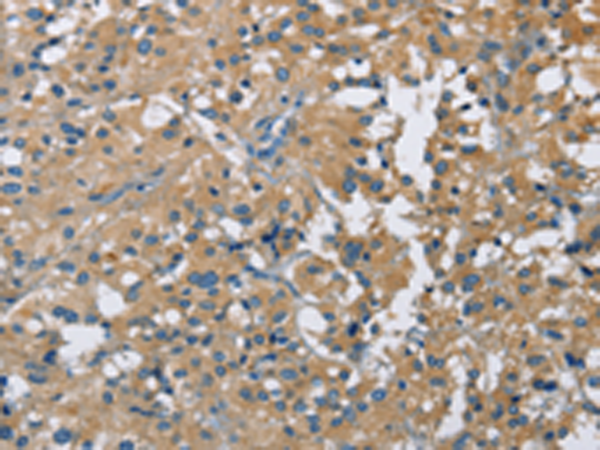

分类: 科研抗体货号: P01124别名: BCSC1; BCSC-1; LOH11CR2A应用: IHC反应种属: Human